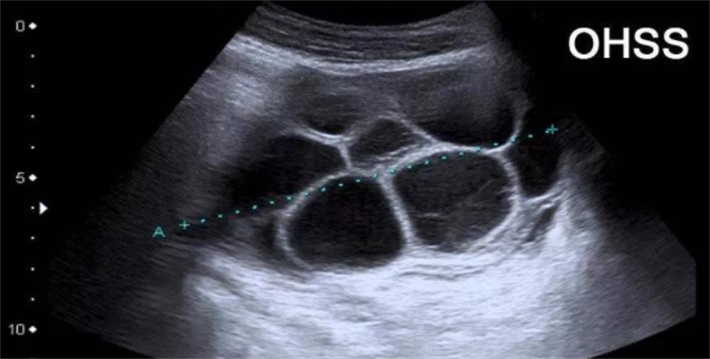

2.卵巢过度刺激综合征

这是一种因卵泡在卵巢内过度发育而引发的医源性状况。女性卵巢显著增大,可能伴有腹水、腹胀、恶心等不适症状,严重时可能出现血液浓缩、电解质紊乱及血栓形成等并发症,需要及时医疗干预。